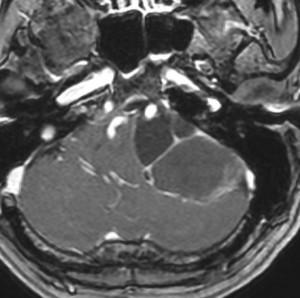

聴神経腫瘍でまず手術が必要なのは巨大なものです。この4枚の写真は私が実際に手術をした患者さんのものです。脳幹部という脳の最も大切なところが腫瘍によって圧迫されて変形しているのが特徴です。右上のものはのう胞性腫瘍なので大きさの割に手術のリスクは高くありませんが,左上のものは実質性で出血性のものですごくリスクが高い手術でした。左下のものは普通のリスク。右下のものは超高難易度のものです。

この腫瘍は脳幹部変形がとても強く,大きいので手術摘出するしか選択肢はありません

- 脳幹部の変形が高度な大きな腫瘍になると手術するしかありません

- 4cmを超えると危険だと考えてください